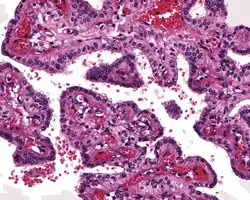

The microscopic appearance shows an unencapsulated, destructive growth, remodeling and invading bone. The tumor is arranged as simple, broad, non-complex papillary projections without large cystic spaces. The spaces are often fluid filled, have extravasated erythrocytes and/or inspissated material. The cells are cuboidal, usually single layered along the papillary structures, showing indistinct cell borders. The nuclei are round and hyperchromatic.[1][3][10][11]